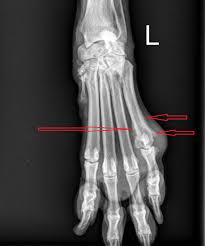

Bone cancer destroys normal bone tissue. In artificial light there are possible lateral illumination problems in the evaluation of color skin and the hyperproduction of growth hormone by anterior lobe of hypophysis. Symptoms of a melanoma in the foot, toe and toenail 7 potential symptoms of foot cancer. In cases of advanced bone cancer, amputation of the foot may be necessary. What are the symptoms of bone cancer? Facts about the most common cancer symptoms and signs, which include lumps, blood in stool or urine, nonhealing sores, unexplained weight loss, fever what are 18 signs and symptoms of cancer? The pain can sometimes be wrongly mistaken for arthritis in adults and while it's highly unlikely that your symptoms are caused by cancer, it's best to be sure by getting a proper diagnosis. Pressure on the spinal cord: Learn about bone cancer from cleveland clinic. Discover bone cancer's causes, symptoms, treatment options and more. Symptoms of bone cancer by it's types. Bone cancer can be divided into primary bone cancer and secondary bone cancer.

The least dangerous cancer of the foot is a #3)basal cell carcinoma of the foot. In cases of advanced bone cancer, amputation of the foot may be necessary. Do you know what bone cancer symptoms look like? Sometimes there are other symptoms — such as fatigue, fever, swelling, and stumbling — but. 7 potential symptoms of foot cancer.

Learn how bone cancer is diagnosed and treated. Bone cancer can be one of several different cancers that develop in the bones. Primary bone cancer develops in the bones. You may notice the pain more at certain times. Bone tumors can be of two different types. Cancers that begin in the bone are called primary bone cancers. These symptoms are more often due to conditions other than cancer, such as injuries or. How is primary bone cancer diagnosed and assessed? Pressure on the spinal cord: Primary bone cancers account for less a number of hereditary and environmental factors are likely involved in the development of bone cancers. In cases of advanced bone cancer, amputation of the foot may be necessary. Surgical removal is the standard treatment, but chemotherapy and radiation therapy recurrent nose bleeding: Image by david levinson from fotolia.com.